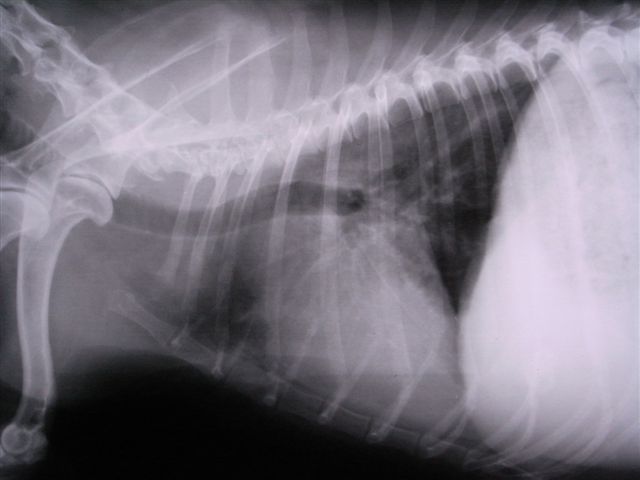

2日後のレントゲン像

気管の蛇行は見られるが肺後部の肺炎像は小さくなった。

咳もほとんどしなくなった

現在、抗生剤、ステロイド剤で維持できている。